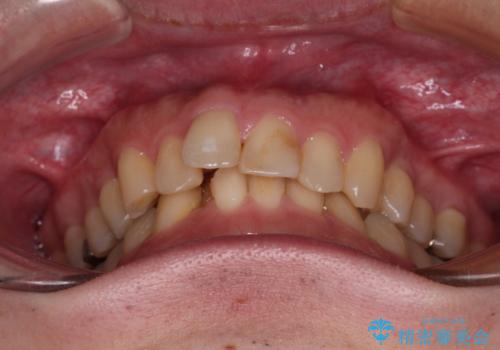

- 深い咬み合わせによる食いしばりで、顎関節や頭が痛むことがあるとのことで来院された患者様です。

歯ぎしりができないくらい強い食いしばりの咬合状態であったため、奥歯の歯軸を起き上がらせることで咬合を挙上させ、歯ぎしりができるようにしていくこととしました。

下顎が左側にずれているため、上下正中は最大限合わせられるところまで合わせるゴールとなりました。